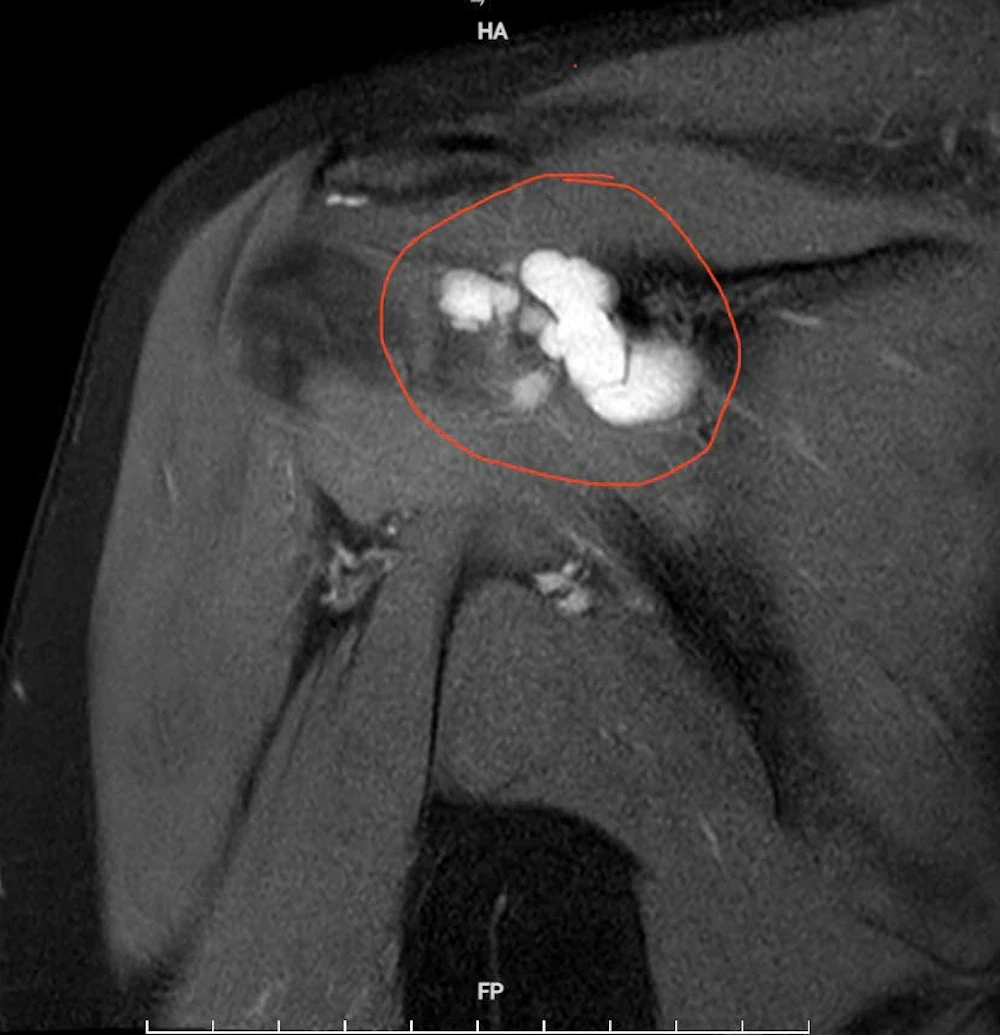

Qua thăm khám lâm sàng kết hợp chẩn đoán hình ảnh, các bác sĩ xác định bệnh nhân mắc u bao hoạt dịch khớp vai phải - một bệnh lý ít gặp trong thực hành lâm sàng. Kết quả chụp cộng hưởng từ (MRI) cho thấy khối u kích thước khoảng 4×2 cm, gây hẹp khoang mỏm cùng vai và chèn ép các cấu trúc xung quanh.

Hình ảnh chụp cộng hưởng từ (MRI) khối u kích thước khoảng 4×2 cm gây hẹp khoang mỏm cùng vai, chèn ép các cấu trúc xung quanh.